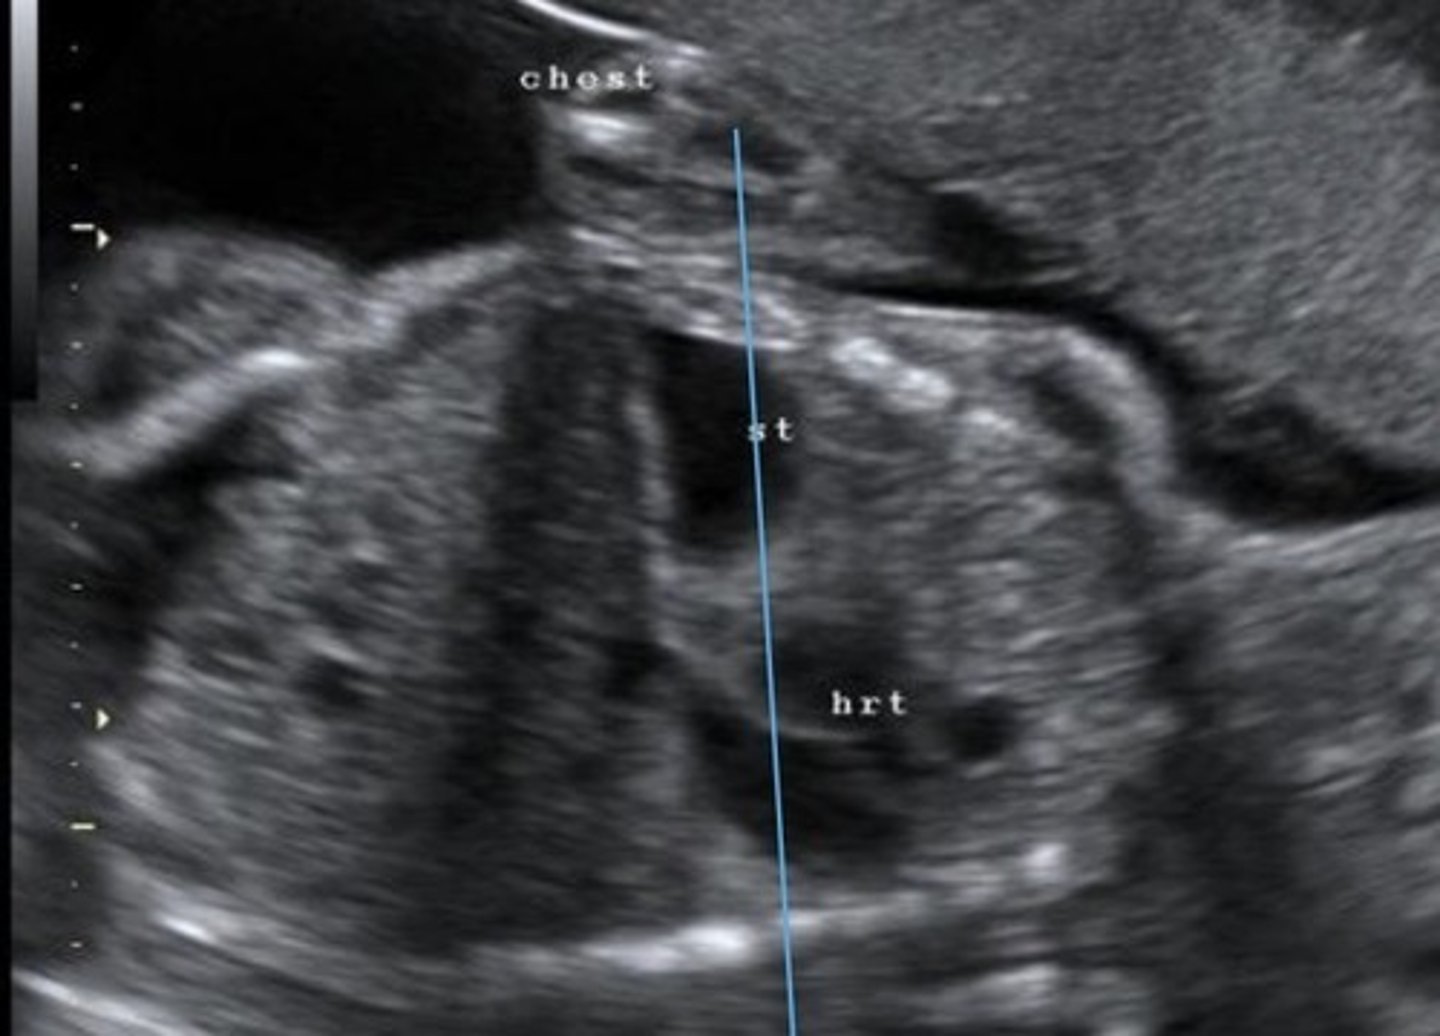

Diaphragmatic Hernia

Herniation of abdominal organs into thoracic cavity through defect in diaphragm